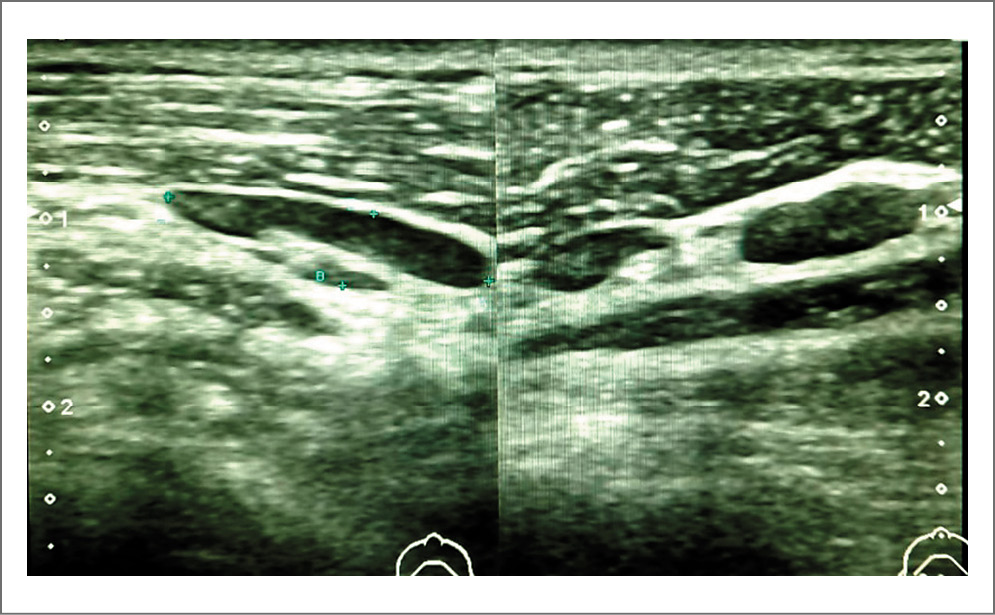

Выполнено ультразвуковое исследование периферических лимфоузлов 08.10.2021; картина представлена на рис. 5–8.

Рис. 8. Метастаз в лимфоузел. Рядом с патологическим образованием в проекции поднижнечелюстной железы справа лоцируется лимфоузел размером 24,6×8×14 мм с наличием в структуре нескольких гиперэхогенных аваскулярных очагов овоидной формы с четким ровным контуром размером 9,6×6,7 мм. Средостение лимфоузла не дифференцируется.